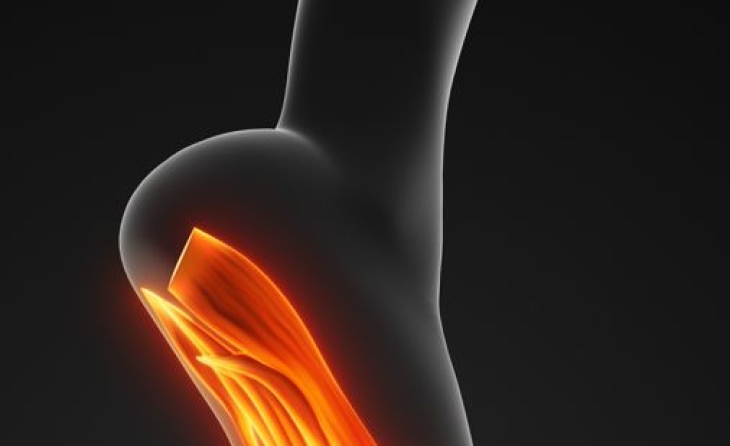

Πρόκειται για μία πολύ επώδυνη φλεγμονή στην πελματιαία απονεύρωση, η οποία είναι τμήμα της πελματιαίας περιτονίας που συνδέει, ως πυκνός ινώδης ιστός, την πτέρνα με τις κεφαλές των πέντε μεταταρσίων του άκρου ποδός. Η πελματιαία απονεύρωση βρίσκεται μονιμά σε τάση, διατηρώντας με τον τρόπο αυτό την ποδική καμάρα. Η πάθηση ανήκει στα σύνδρομα υπέρχρησης και αφορά σε φλεγμονή στο σημείο έκφυσης της απονεύρωσης από την πτέρνα. Είναι μια από τις συχνότερες αιτίες πόνου στην περιοχή της πτέρνας.